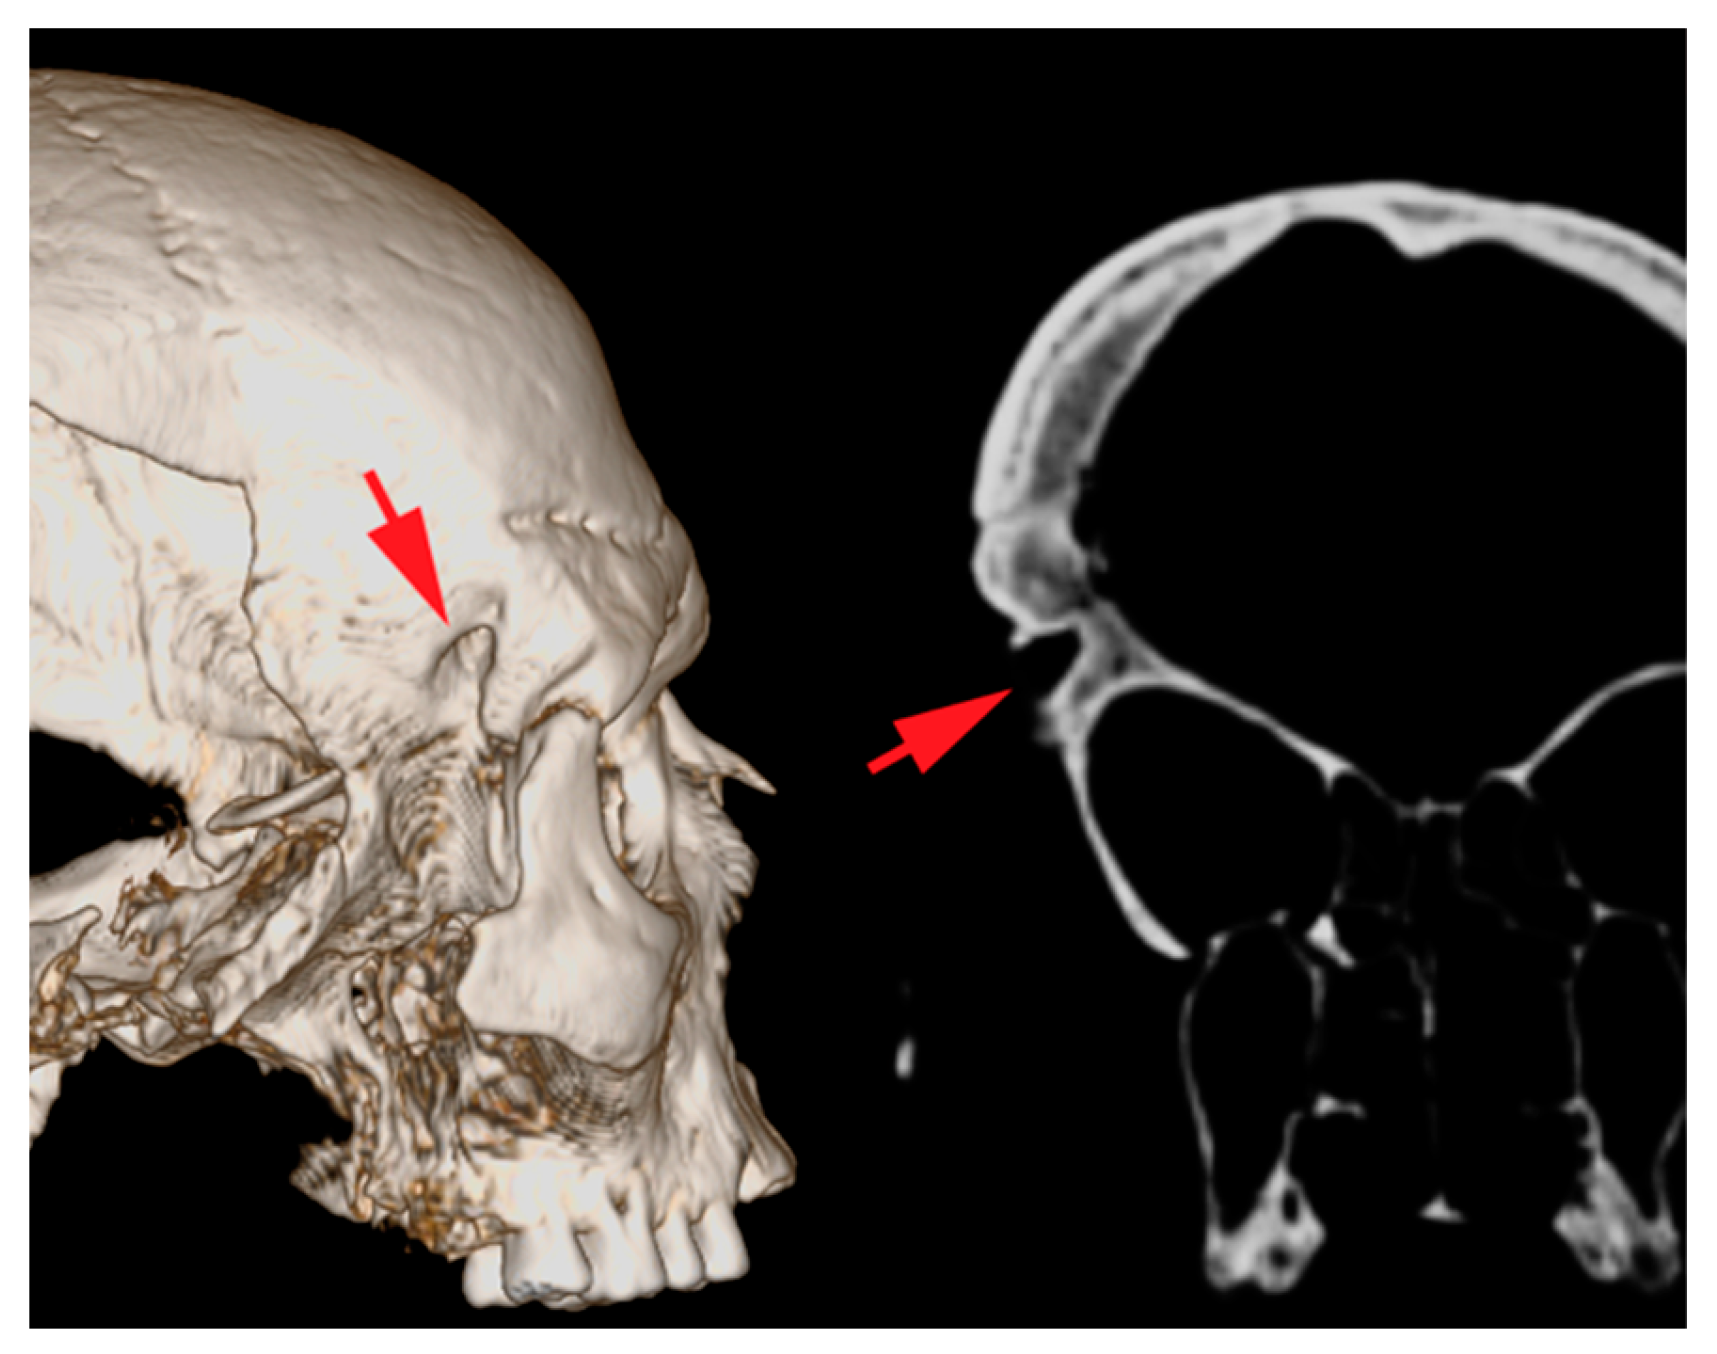

3.1. Anthropological and Radiographic Analysis